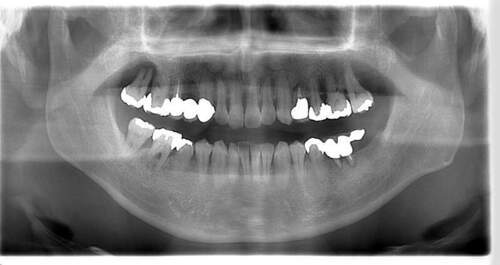

インプラント治療の症例1

レントゲン写真

- 透過像

| 年齢 | 50代・男性 |

|---|---|

| 主訴 | 右下歯が疼く |

| 治療内容 | ・右下6番インプラント ※1:FGG(遊離歯肉移植術)とは、足りない歯ぐきを上顎から上皮を切り取り移植する外科手術 |

| 治療費 | 合計:902,000円(税込) ■内訳 |

| 治療期間 | 9ヵ月 |

| 治療方針 | 右下の当該歯は歯根破折により保存不可能と診断しました。歯周疾患も伴っていたため抜歯後に骨吸収※1が大きく起こることが予測できました。チタンメッシュ併用骨再生誘導法(GBR※2)を選択しインプラント埋入と同時に行い自然な歯槽骨のラインを再現しました。またGBRを行う際にインプラント辺縁の付着歯肉の減少が起こる為、遊離歯肉移植術(FGG※3)を行い清掃性を考慮した形態に仕上げました。 ■治療方針の解説 治療した右下の歯をレントゲンで撮影したところ根本の部分に黒く写る箇所があり「根尖性慢性周囲炎※1」と診断。また歯周病も進行していました。 ※1 骨吸収・・・歯槽骨という歯を支える骨がなくなっていくこと |

| 担当者所見 | 主訴の右下だけでなく歯茎の腫れ、発赤があり不良補綴や不良充填など他にも治療箇所が多数ありました。プラークコントロールが不良であった為まずはブラッシング指導を行いセルフケアの重要性を理解していただくところからスタートしました。 右下6番の歯はインプラント治療を行なった結果審美的にも機能的にも患者様の満足を得ることができました。骨造成と歯肉移植も行なった為インプラントを支える十分な歯周組織の獲得ができたと思っております。 |